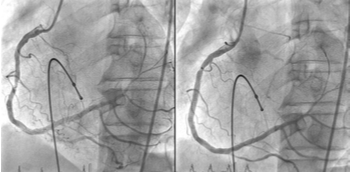

La cardiología intervencionista ha evolucionado de forma espectacular en los últimos años habiendo cambiado el enfoque en el manejo de la cardiopatía isquémica y aportando soluciones mucho menos agresivas en la cardiopatía estructural. Ello ha sido debido al...

Aunque la tasa de mortalidad relacionada con la cardiopatía isquémica en Europa está declinando en los últimos años, continúa siendo la causa de muerte aislada más frecuente a nivel mundial y supone unos 1,8 millones de muertes o el 20% de las mismas anualmente sólo...